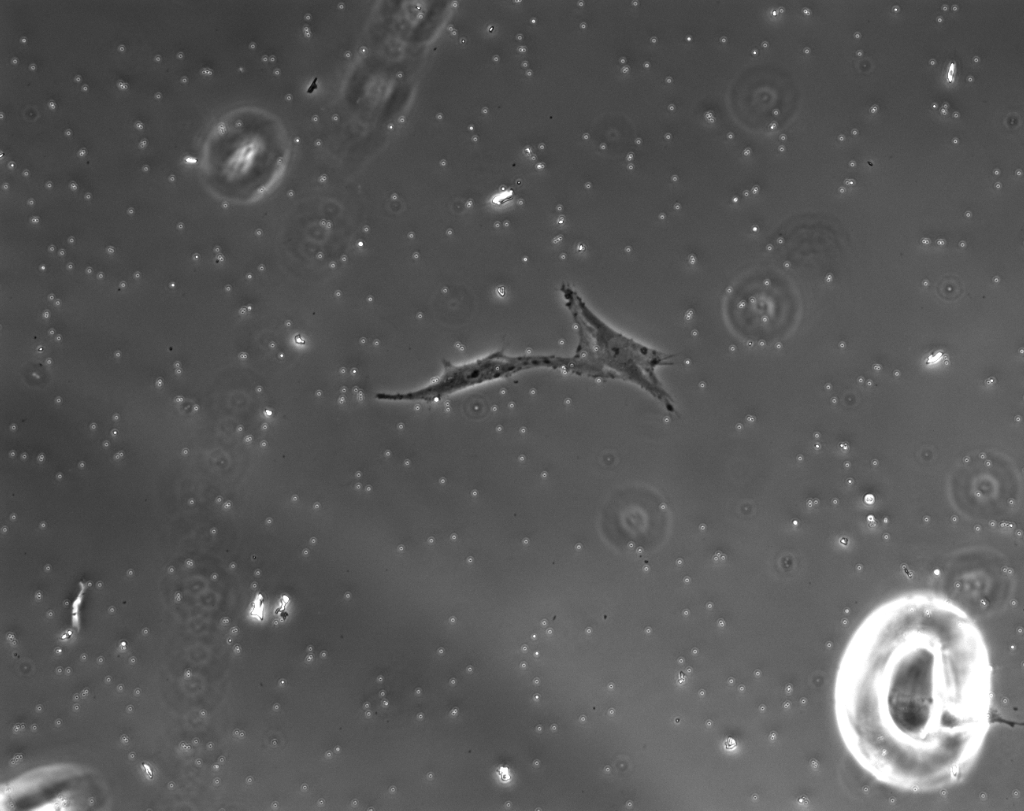

A high contrast map between cells and background is then obtained, as shown in Figure 2. Therefore, cell segmentation is accomplished by simply thresholding.

Later on, another segmentation method was developed by analyzing camera exposure [56], which computes Maximally Stable Extremal Regions(MSER) [57] under each exposure settings. It gets a binary map of cells by accumulating these obtained MMSERs using the frequency of pixels in each MMSER. The final segmentation is accomplished by applying a Graph-cut on MMSER.